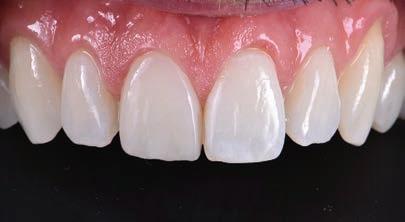

On clinical examination, UR1 was responsive to viability testing, and did not present periapical lesions on the radiograph performed on the same day (Figure 1). UR1 was discoloured and in a more palatal position than the contralateral central UL1 (Figure 2). The aesthetic analysis highlighted an asymmetry of the gingival zenith between UR1 and UL1. Through the use of a periodontal probe, after plexus anaesthesia, the altered passive eruption of the type IA junctional epithelium was confirmed according to the classification of Coslet et al. (Figure 3).

element, it was decided to carry out a direct composite restoration following planning and a diagnostic wax-up of the case.

The finishing and polishing procedures were carried out trying to emulate the transition lines of UL1 (Figures 12 and 13).

The patient was checked again after 21 days (Figures 14 and 15) and 12 months (Figure 16) to evaluate the aesthetic result in shape and colour.